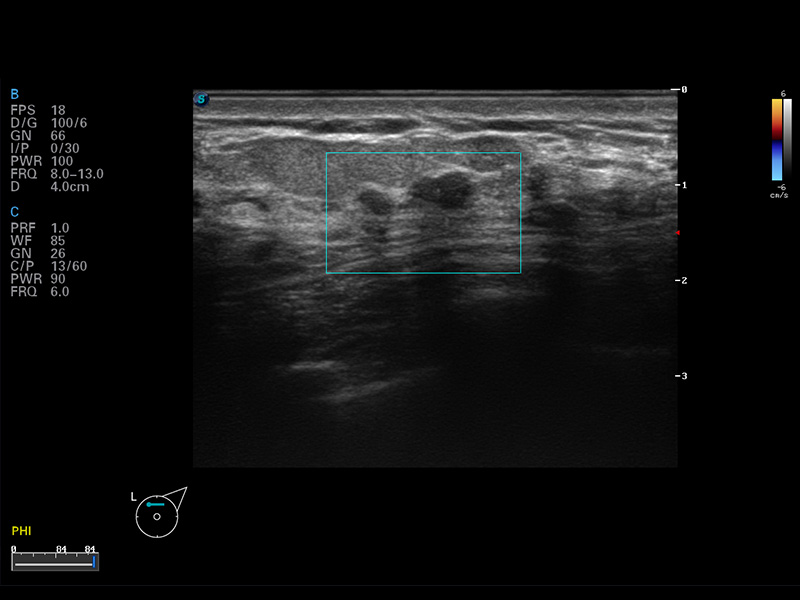

S8 EXP便携式彩色多普勒超声诊断仪是1xBET研发的高端全身应用型便携彩超。高通道的VIS平台融合可视化(Visual)、智能化(Intelligent)和人性化(Smart)的特点,配以1xBET自主研发生产的探头大家族,使您能够快速、准确的获得病人信息,提高工作效率的同时减轻疲劳。

μ-Scan微米成像